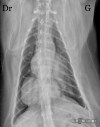

Latérale du thorax